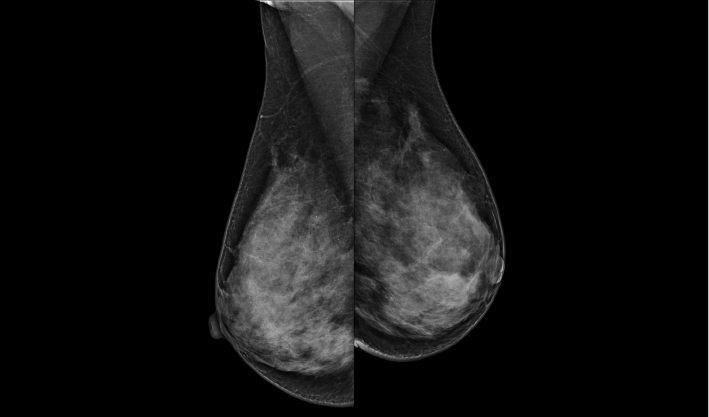

頭尾位(CC位) 內外斜位(MLO位) 補充體位(根據需求)

一鍵式視圖切換

致力于致密乳腺的早期癌變篩查和微鈣化簇精準定性。